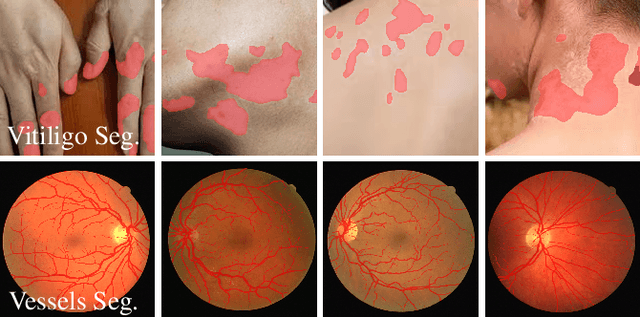

Abstract:High-quality annotated data plays a crucial role in achieving accurate segmentation. However, such data for medical image segmentation are often scarce due to the time-consuming and labor-intensive nature of manual annotation. To address this challenge, we propose the Adaptive Frequency Domain Alignment Network (AFDAN)--a novel domain adaptation framework designed to align features in the frequency domain and alleviate data scarcity. AFDAN integrates three core components to enable robust cross-domain knowledge transfer: an Adversarial Domain Learning Module that transfers features from the source to the target domain; a Source-Target Frequency Fusion Module that blends frequency representations across domains; and a Spatial-Frequency Integration Module that combines both frequency and spatial features to further enhance segmentation accuracy across domains. Extensive experiments demonstrate the effectiveness of AFDAN: it achieves an Intersection over Union (IoU) of 90.9% for vitiligo segmentation in the newly constructed VITILIGO2025 dataset and a competitive IoU of 82.6% on the retinal vessel segmentation benchmark DRIVE, surpassing existing state-of-the-art approaches.